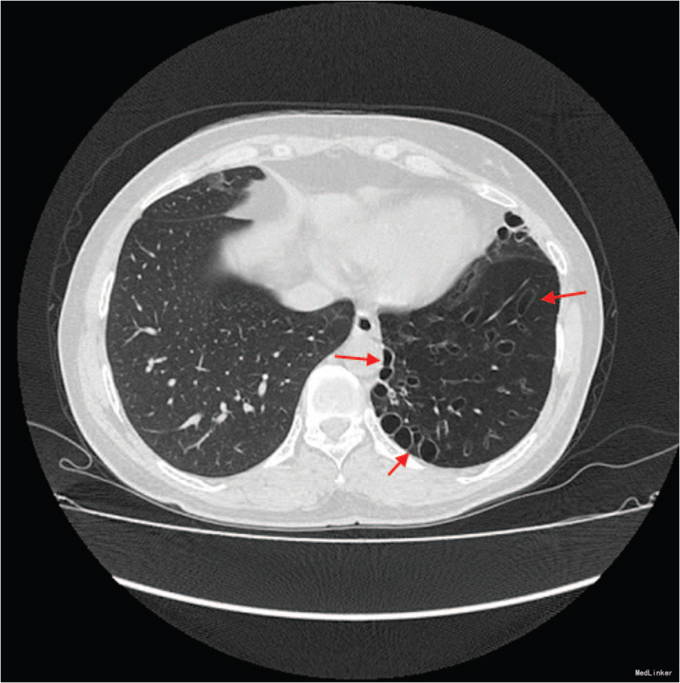

双肺听诊闻及左肺底部湿罗音及双肺呼气相哮鸣音。肺功能检测提示COPD,中度气流阻塞。胸片提示患侧肺透明度增加,支气管扩张及左肺体积缩小。胸部CT提示肺动脉发育不良,支气管扩张,左肺体积减小及密度降低(如图)。

诊断斯-詹综合征伴COPD。给予联合吸入长效β-受体激动剂和皮质类固醇治疗。